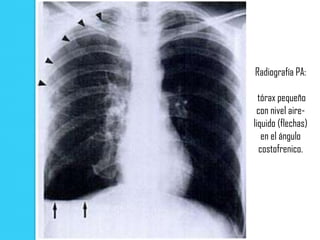

   Un pequeño nivel aire-liquido en el ángulo costofrenico (que

se manifiesta como un línea horizontal de interfase aire-

liquido) puede ser el indicio de un neumotórax sutil.

Radiografía PA:

tórax pequeño

con nivel aire-

liquido (flechas)

en el ángulo

costofrenico.